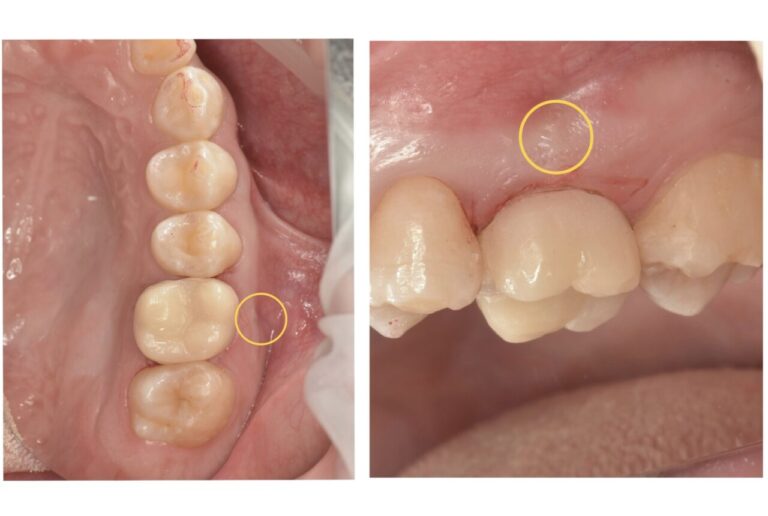

詰め物の下の歯茎に出来物ができた患者様の症例

部位は右下の5番目です。

根っこの先の骨が溶けて黒くなっているのが確認できます。

こちらが膿が溜まった後出口として、歯茎の表面に出来物(フィステル)ができた様子です。

この歯は神経が残っている歯でしたが、残念ながら失活(神経が死んでしまうこと)してしまっていました。その為、歯の根っこの中を消毒する処置を行います。 -

根管治療を行った後、骨が回復するまで6ヶ月ほど経過観察を行います。こちらは治療後6ヶ月のレントゲンとCTの写真です。

-

まだ少し黒い影はあるものの、薄く骨のようなものがモヤっとできており、溶けていた根っこの先の骨が大きく回復傾向にあるのがわかります。

大きく腫れてしまっていた歯茎も根っこの膿の消失とともに治癒しました。